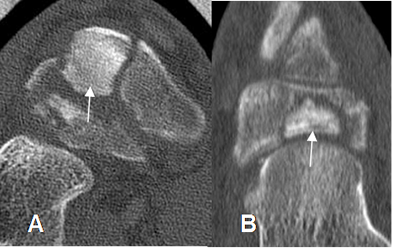

Fig 57. Necrosis del escafoides.

A: TAC corte axial y B: TAC reconstrucción coronal El mismo paciente anterior con seudoartrosis del escafoides y fragmento denso, por osteonecrosis.